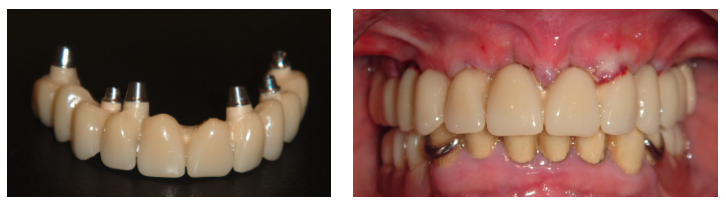

Prótesis fija maxilar con carga inmediata

Paciente con fracaso de rehabilitación maxilar con puentes y coronas dento soportadas de maxilar superior. En una sola fase se hacen las exodoncias, colocación de implantes y dientes fijos en el día (carga inmediata). Prótesis definitiva de metal-cerámica.

Foto de la carga inmediata antes y después de su colocación, el mismo día de la instalación de los implantes.